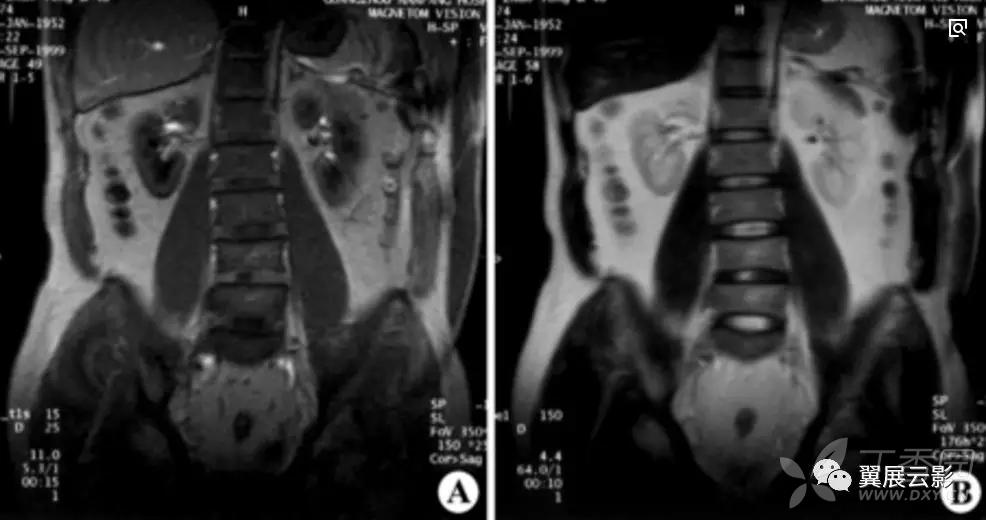

MixiMRI勉強会 脂肪抑制いろいろ 最近やっと勉強する気になったのですが、疑問が次から次へと出てきます。ここでは脂肪抑制についてお聞きしたいと思います。 脂肪抑制にもいろいろありますよね。 T2、PD、T1など。また、SE系、GRE系の違いもありま. ・骨盤部ではmriを,腹部ではctを第一選択にする. ・t1強調画像ではt1が長いほど磁化の回復が遅れるため信号が低く(黒く),t2強調画像ではt2 が長いほど磁化の減衰が遅れるため信号が高く(白く)描出される.t1とt2の組み合わせで組 t1強調画像はctの画像と似ており、脳の解剖学的な構造が見やすいという特徴があります。. 造影剤投与によりT1緩和時間が大きく短縮されますので基本的に脂肪抑制T1強調画像をベースに撮影が行われます。 ③実際の症例を提示します。 1) Stage I 腎細胞癌のdynamic MRI画像です。 左腎臓上極に1cm大の遷延性濃染する腫瘍を認めます。.

MRIは、磁気共鳴画像(Magnetic Resonance Imaging)の略称で、 強い磁石 と 電波 を使って体の断層像を撮る検査です。 MRIの原理は、まず強い磁気の中で、患者さんに外から電波を体に加えます。. ・骨盤部ではmriを,腹部ではctを第一選択にする. ・t1強調画像ではt1が長いほど磁化の回復が遅れるため信号が低く(黒く),t2強調画像ではt2 が長いほど磁化の減衰が遅れるため信号が高く(白く)描出される.t1とt2の組み合わせで組織 の成分が推定できる.. Mri造影剤は、mriにおける体内構造の可視性を向上するために使われる造影剤 。 コントラストの強調にはガドリニウムという化合物が最も一般的に使われる。 このmri造影剤は経口投与もしくは静脈投与(angio)により体組織内の核の緩和時間を短縮する。.

〈medix vol.50〉 41 1.はじめに mri検査において基本シーケンスはt2強調画像とt1強調 画像である。かかりつけ医の医療の場において、診断能向上の. 頭部MRI の基礎 -頭部MRI で撮られる各画像について- 友愛会南部病院 仁井田 明 要旨 現在、日常的に撮影されている頭部MRI(Magnetic resonance imaging :磁気 共鳴画像法)画像にはT1 強調像(T1WI)、T2 強調像(T2WI)、プロトン密度強 調像(PDWI)あるいはFLAIR(FLuid-Attenuated Inversion Recovery)像. 3T MRIの組織コントラスト能の特徴 T1強調画像 de Bazelaireらの研究 1) によると,腹部領域における3Tと1.5Tの緩和時間の違いは,肝臓,脾臓,膵臓では,3TでT1値が著明に延長するのに対し,筋肉では緩和時間に差がなく,結果的に,3Tでは肝臓,膵臓,筋肉でのT1値の差が少なくなる。.